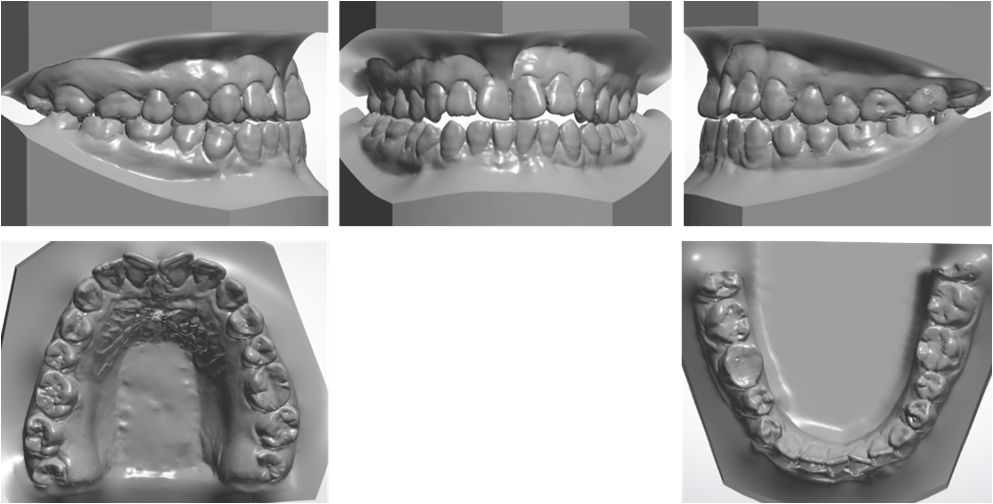

上下牙弓呈方圆形;双侧尖牙、磨牙III类关系;21牙与31牙呈切合;前牙呈现约1 mm的局部开合;下颌中线较上颌中线左偏1 mm。

模型分析:

上颌拥挤度:1.5 mm,下颌拥挤度:1.5 mm。Bolton指数:全牙比为86.70%,前牙比为75.5%。患者上下颌牙列均存在前牙段轻度的拥挤,前牙和全牙的bolton指数均偏小,提示上颌牙齿牙冠宽度偏大。